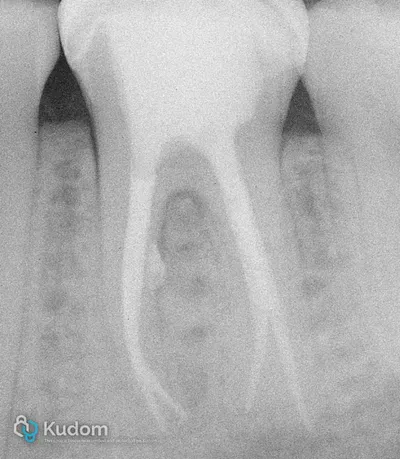

Trattamento endodontico di un primo molare mascellare, con attenzione alla corretta detersione, sagomatura e otturazione.